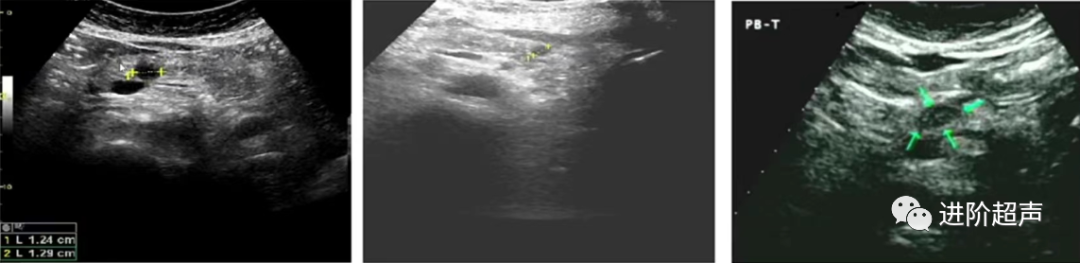

胰腺前后径测量(胰腺长轴切面)和胰管测量:

胰头前后径

下腔静脉前、胰腺后缘中点向前的垂直线

胰体前后径

腹主动脉和肠系膜上动脉圆心连线通过胰体前后缘的距离

胰尾前后径

过腹主动脉圆心,并和上述两圆心相交呈45°的直线上取胰尾前后缘距离

胰管

胰管显示最宽处

正常胰管内径(前后径)体部不大于2mm

头颈部不大于3mm